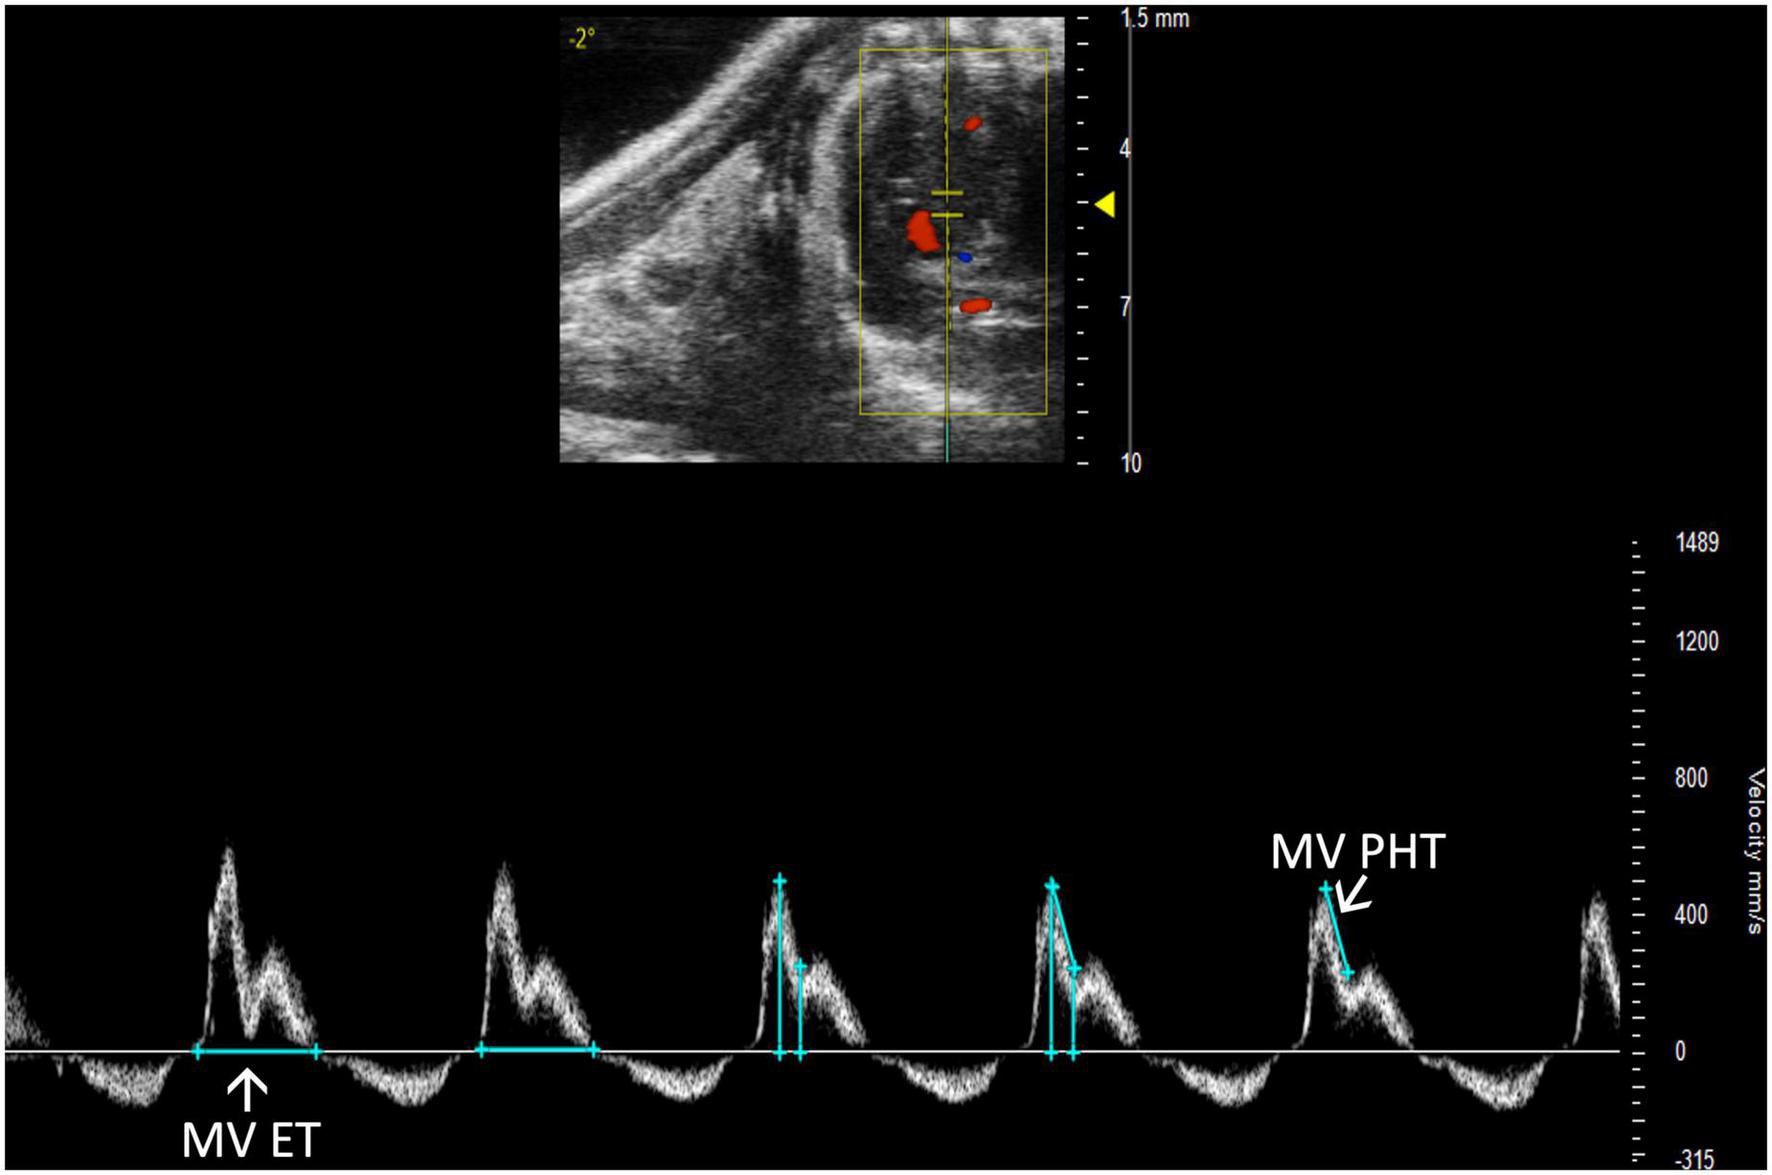

2.3.3.2 Mitral valve pressure half time

Mitral stenosis is another disease that is not well-replicated in mice. However, mitral valve pressure half time (MV PHT) is a potentially useful parameter in the setting of mitral stenosis (10). MV PHT is the time interval, in milliseconds, for the maximum mitral gradient to reduce to half the maximum initial value. It is most accurately measured in a PW Doppler image of the mitral valve by measuring maximum velocity, calculating half of the maximum velocity, and dropping another velocity measurement on the mitral valve curve equal to half of the maximum velocity. Finally, the peaks of the velocity measurements are measured as MV PHT, and the velocity measurements can be deleted (Figure 12).

FIGURE 12

Pulsed wave (PW) Doppler mode image showing mitral valve pressure half time (MV PHT), a measure of mitral stenosis and mitral valve ejection time (MV ET), the duration of diastolic filling in the left ventricle.

2.3.3.3 Mitral valve ejection time

Mitral valve ejection time (MV ET) is equal to the duration of diastolic filling of the LV; therefore, can be used to further characterize diastolic dysfunction. MV ET is measured at the end of IVRT to the beginning of IVCT on a PW Doppler of the mitral valve (Figure 12).